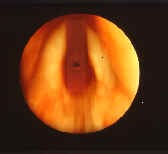

- For subglottic stenosis, recognize the value and significance of the Cotton/Myer grading scale to describe subglottic stenosis.

- Laryngeal stenosis: A 27-week ex-preemie, born at 900 grams with severe BPD status/post a tracheotomy done at 10 weeks of age for failure to extubate, presents to you at 11 months of age for evaluation. The child is no longer requiring oxygen, has gained weight up to 8 kg, has GERD controlled on medications, and is no longer on bronchodilators. Endoscopy reveals an eccentric narrowing at the level of the cricoid and first tracheal ring along with a large suprastomal granuloma, with narrowing estimated at about 85% and predominantly anterior.

- Cotton class III subglottic stenosis, acquired.

- Treatment at this time would involve consideration of a single-stage laryngotracheal reconstruction with autologous costal cartilage grafting. Need to make certain that the GERD is under optimal control, that the child’s pulmonary reserve is adequate, and that all other medical conditions are stable before proceeding with reconstruction.